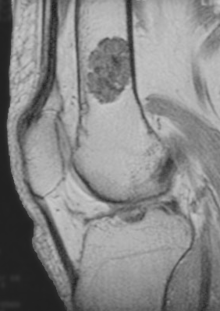

An enchondroma is a cartilage cyst found in the bone marrow. Typically, enchondroma is discovered on an X-ray scan. Enchondromas have a characteristic appearance on Magnetic Resonance Imaging (MRI) as well. They have also been reported to cause increased uptake on PET examination.

- magnetic resonance imaging (MRI)[1] - a diagnostic procedure that uses a combination of large magnets, radiofrequencies, and a computer to produce detailed images of organs and structures within the body. This test is done to rule out any associated abnormalities of the spinal cord and nerves.